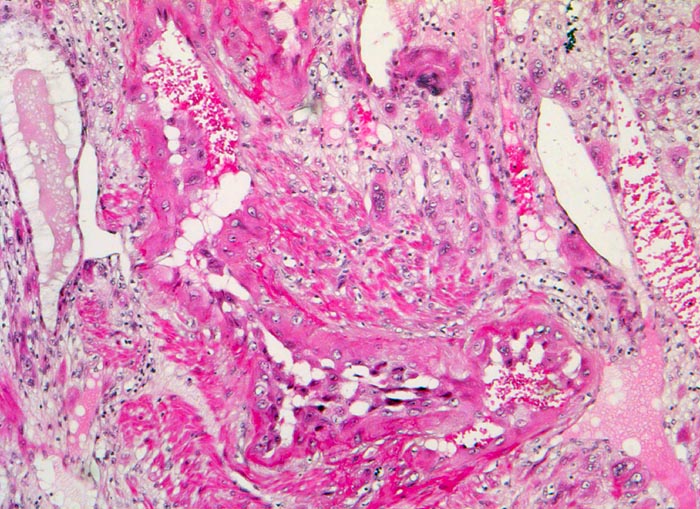

Morphologische Merkmale:

• Myometrium bedeckt von dezidualisiertem Endometriumstroma der Dezidua basalis.

• Invasion des Myometriums durch intermediären extravillösen Trophoblast.

• Fibrinoidschicht.

• Chorionzotten, ein Teil davon verankert mit dem dezidual transformierten Endometrium = Dezidua basalis (Haftzotten).

• Choriondeckplatte.

• Rechts oben Anteile des Chorion laeve.